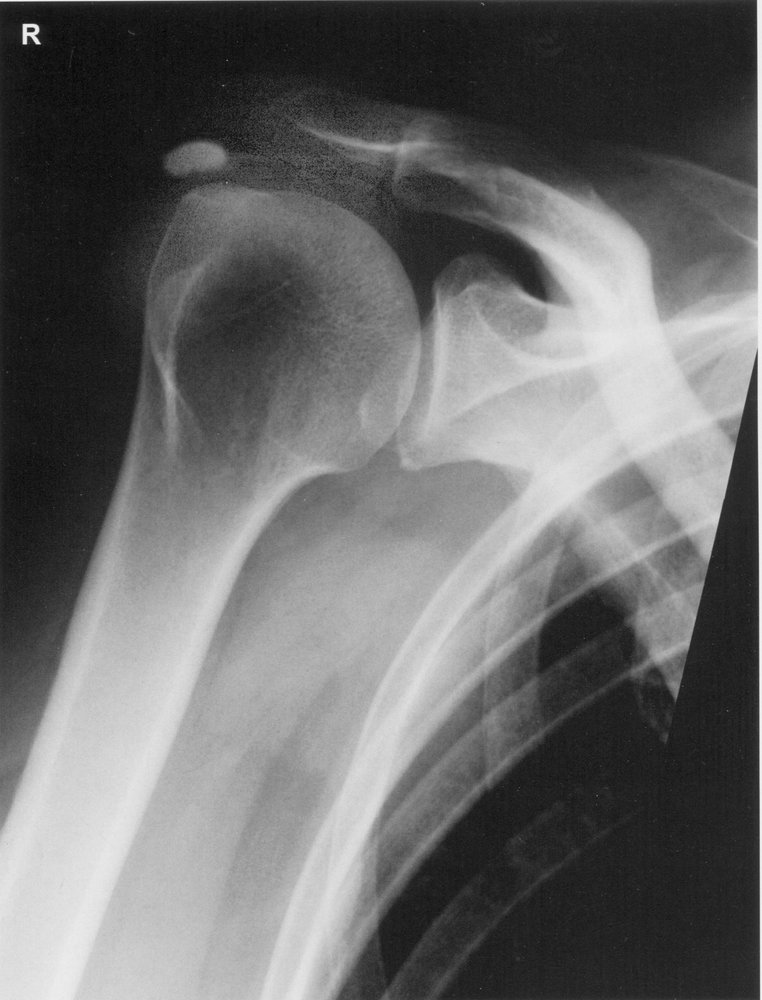

• Imaging [12]

• X-ray of the affected joint [3]

• Initial imaging modality of choice

• Large deposits of calcifications within the articular cartilage

Periarticular calcium deposits may be asymptomatic and detected incidentally. [2]